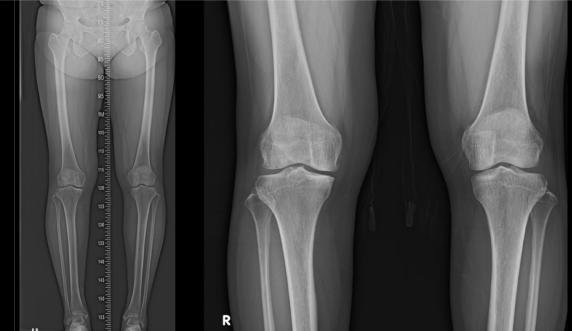

수술 전 환자의 상태

수술 후 1년